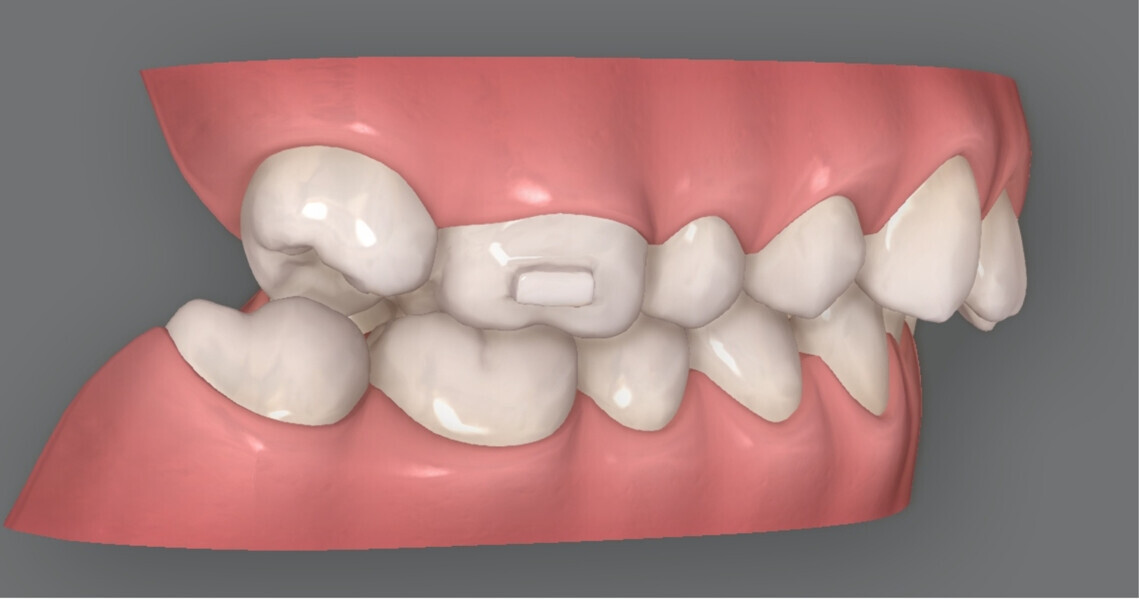

Since a one-phase treatment approach was planned, an additional scan was taken immediately afterwards to produce the aligners (Invisalign, Align Technology). The goal was to achieve simultaneous bilateral molar distalisation and alignment of all the teeth using the aligners. To facilitate this, a distalisation rate of 0.2 mm per week was set, corresponding to a quarter turn of a screw with a thread pitch of 0.8 mm. The distalisation was planned asymmetrically because the molars in the maxillary right quadrant had drifted further mesially than those in the maxillary left quadrant (Fig. 6). The patient was given specific instructions on which aligner to activate the distaliser screws with. The distalisation was completed by the 20th aligner.

Fig. 6: Skeletally anchored distaliser used simultaneously with aligners. Greater distalisation was performed in the maxillary right quadrant than in the maxillary left quadrant.